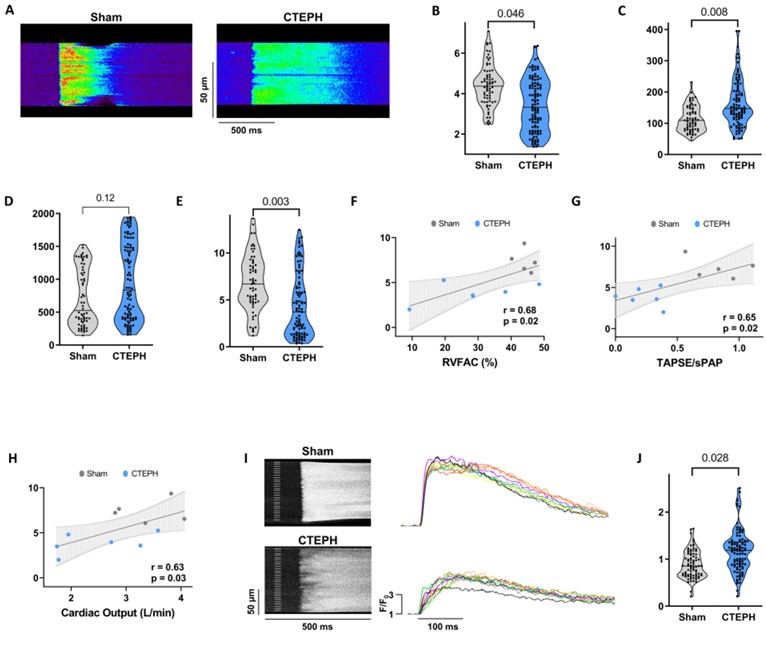

Dynamic changes in calcium cycling drive RV dysfunction in a pre-clinical model of pulmonary hypertension ahajournals.org/doi/full/10.11… #AHAJournals Ana M Gómez Julien Grynblat InsermU999